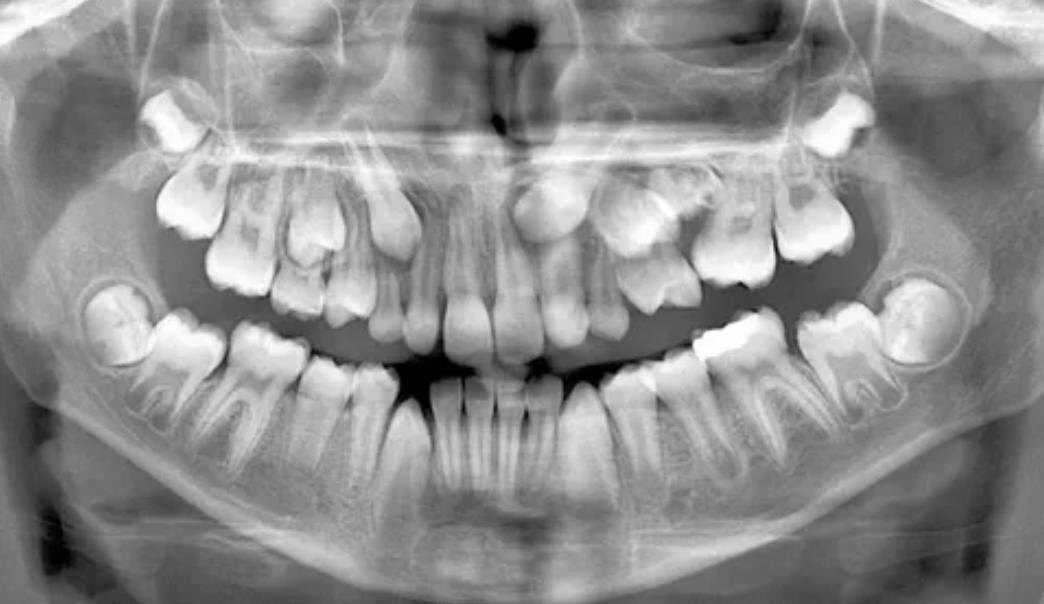

У человека в норме 20 молочных и 32 постоянных зуба (с учетом зубов мудрости). Если их больше — это гипердонтия.

Чаще всего они скрыты в десне и становятся "зубами-невидимками", о существовании которых родители даже не подозревают.

• При плановых обследованиях: Благодаря современным методам диагностики, родители все чаще делают панорамные снимки (ОПТГ) или компьютерную томографию (КТ) детям в раннем возрасте, что позволяет выявить проблему до ее явных проявлений.

• Тренд на раннюю диагностику: Современные родители стали более осознанными и чаще водят детей на профилактические осмотры. Акцент смещается с "лечим, когда болит" на "предупреждаем патологии прикуса". Компьютерная томография (КТ) и панорамные снимки (ОПТГ) в 6-7 лет становятся нормой, позволяя выявить сверхкомплектные зубы задолго до того, как они нанесут ущерб.